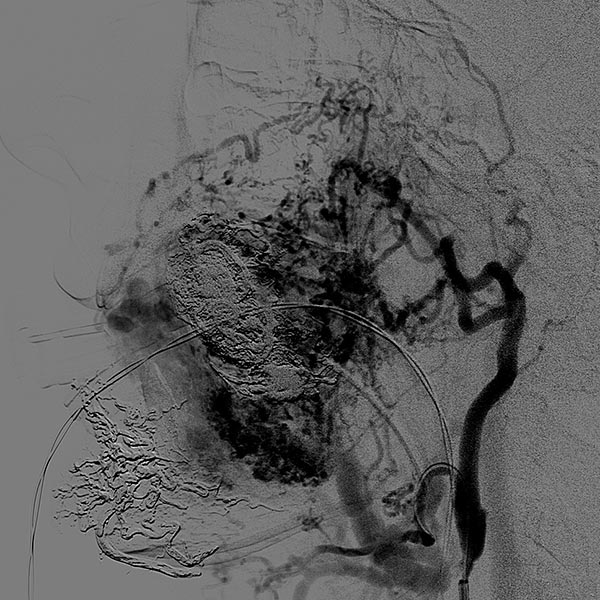

Complete filling of the entire nidus of the AVM using ethylene-vinyl alcohol copolymer (EVOH). This is visible in the radiograph shown here (AP) as a black, reticular radiopaque cast specimen within the occluded AVM vessels.

Filling of the entire nidus of the AVM using ethylene-vinyl alcohol copolymer, which is visible in the radiograph shown here (lateral view) as a black, reticular radiopaque cast within the occluded AVM vessels.